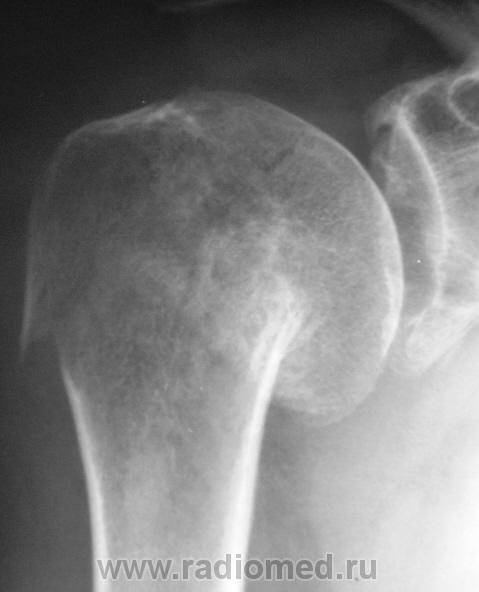

Случай № 1. Пациент направлен хирургом на рентгенографию плечевого сустава. 2 дня тому - травма.

Вколоченный перелом шейки плечевой кости с отрывом большого бугра. Варусная деформация на уровне перелома.

хирургической шейки плеча со смещением дистального отломка краниально.